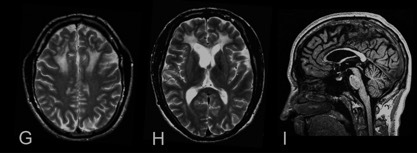

案例 13:54 岁男性,诊断为 ADLD。

图 14 A~B:T2WI 可见小脑深部白质,小脑中脚和脑桥高信号病灶;C~D:FLAIR 提示脑室旁和皮质下白质以及胼胝体压部弥漫高信号伴萎缩;亦可见内囊 [C] 和脑桥 [B] 皮质脊髓束高信号 [箭头]